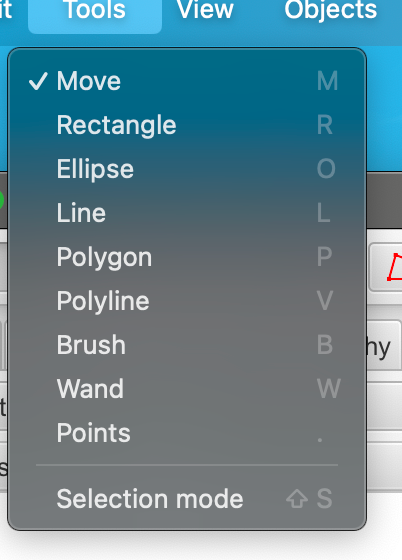

无论哪种方式,您都可以使用快捷键快速激活所需的工具,例如只需按M键即可激活移动工具,B键激活画笔工具,P键激活多边形工具等。您可以在“工具”菜单下看到所有绘图工具的快捷键。

3-1:主要工具

矩形工具

最基本的绘图工具是矩形工具。在图像中点击起始点,然后拖动鼠标到所需矩形对角线的另一端,然后释放。在绘制矩形时按住Shift键将形状约束为正方形。

椭圆工具

椭圆工具的工作方式与矩形工具类似,只是最终提供的是椭圆区域。在绘制椭圆时按住Shift键将形状约束为圆形。

线条工具

可以使用线条工具绘制线条,通过单击一次以确定起始点,然后双击以确定结束点。

多边形工具

多边形工具是绘制区域的好标准。它可以用两种方式使用:

- 点击每个顶点应该的位置

- 点击并拖动以绘制连续线(QuPath会在空间中分割顶点)

前者如果您以后可能想要编辑多边形,并将其顶点拖到不同位置,那么这是更好的选择。后者如果您手稳,并想要绘制更详细的区域,那么这是更好的选择。在绘制同一区域时可以切换。

如果您通过点击并拖动开始一个多边形,那么多边形在释放鼠标按钮时完成。否则,ROI在双击图像上的最终点位置处完成。

多边线工具

多边线工具与多边形工具类似,只是它不是封闭的;它有长度(像一条线),但没有面积。

画笔工具

画笔工具可能是我在注释区域时使用最多的绘图工具。它的原理很简单:每次点击画笔都会选择一个小圆圈,但通过在图像上拖动鼠标,就可以“绘制”区域。

这本来不会引起太大的兴奋,但QuPath中的画笔工具具有一些特别有用的功能:

- 画笔的大小会根据放大倍数进行调整。换句话说,如果您放大,画笔实际上会“绘制”小区域 - 而在放大倍数缩小时,它可以快速标记大区域。

- 在使用画笔时按住Alt键会使它“减去”区域……基本上就像一个橡皮擦(或画笔的等效物)。

- 画笔可以细化使用其他工具绘制的ROI。这可以在加法(正常)或减法(按住Alt键)模式下工作 - 使ROI可以更精确地清理,还可以在现有ROI中创建孔洞。

您可以在设置中更改画笔的绝对大小,也可以选择关闭根据缩放调整大小。